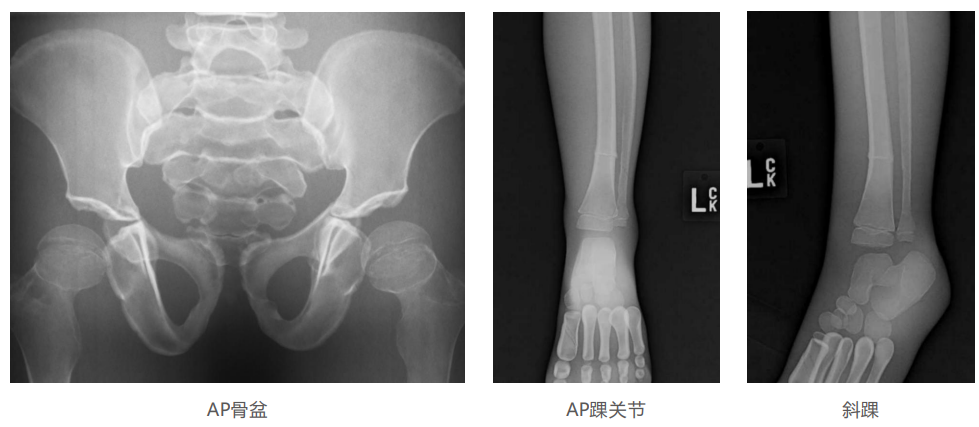

仿真人體模體旨在幫助教學(xué)和提高患者對(duì)體位、準(zhǔn)直和解剖學(xué)的理解,其廣泛的特點(diǎn)有助于安全、高質(zhì)量的人體影像學(xué)的有效指導(dǎo)。

模體的大小和結(jié)構(gòu)都代表了人體模體,使其便攜和易于定位。包括頭、胳膊和腿在內(nèi)的整個(gè)身體。該系列包括六個(gè)部分的模體可單獨(dú)或作為一個(gè)完整的集合。

右肢有伸直或彎曲兩種配置。左臂和左腿可選伴有或不伴有內(nèi)嵌骨折。

骨折版本包含最常見的人體骨折類型 ,包括脛骨扣帶骨折和腓骨普通骨折;

第一跖骨骨折;橈骨切開復(fù)位骨折 ,第二中間趾骨常見骨折。組件由適當(dāng)?shù)木郯滨ズ铜h(huán)氧材料制成,模擬人體組織的X射線衰減特性,用于診斷和治療能量范圍(50 keV - 25 MeV) 。 材料經(jīng)久耐用 ,耐沖擊,適合連續(xù)搬運(yùn)。透明的軟組織有助于解剖標(biāo)志的視覺指示。